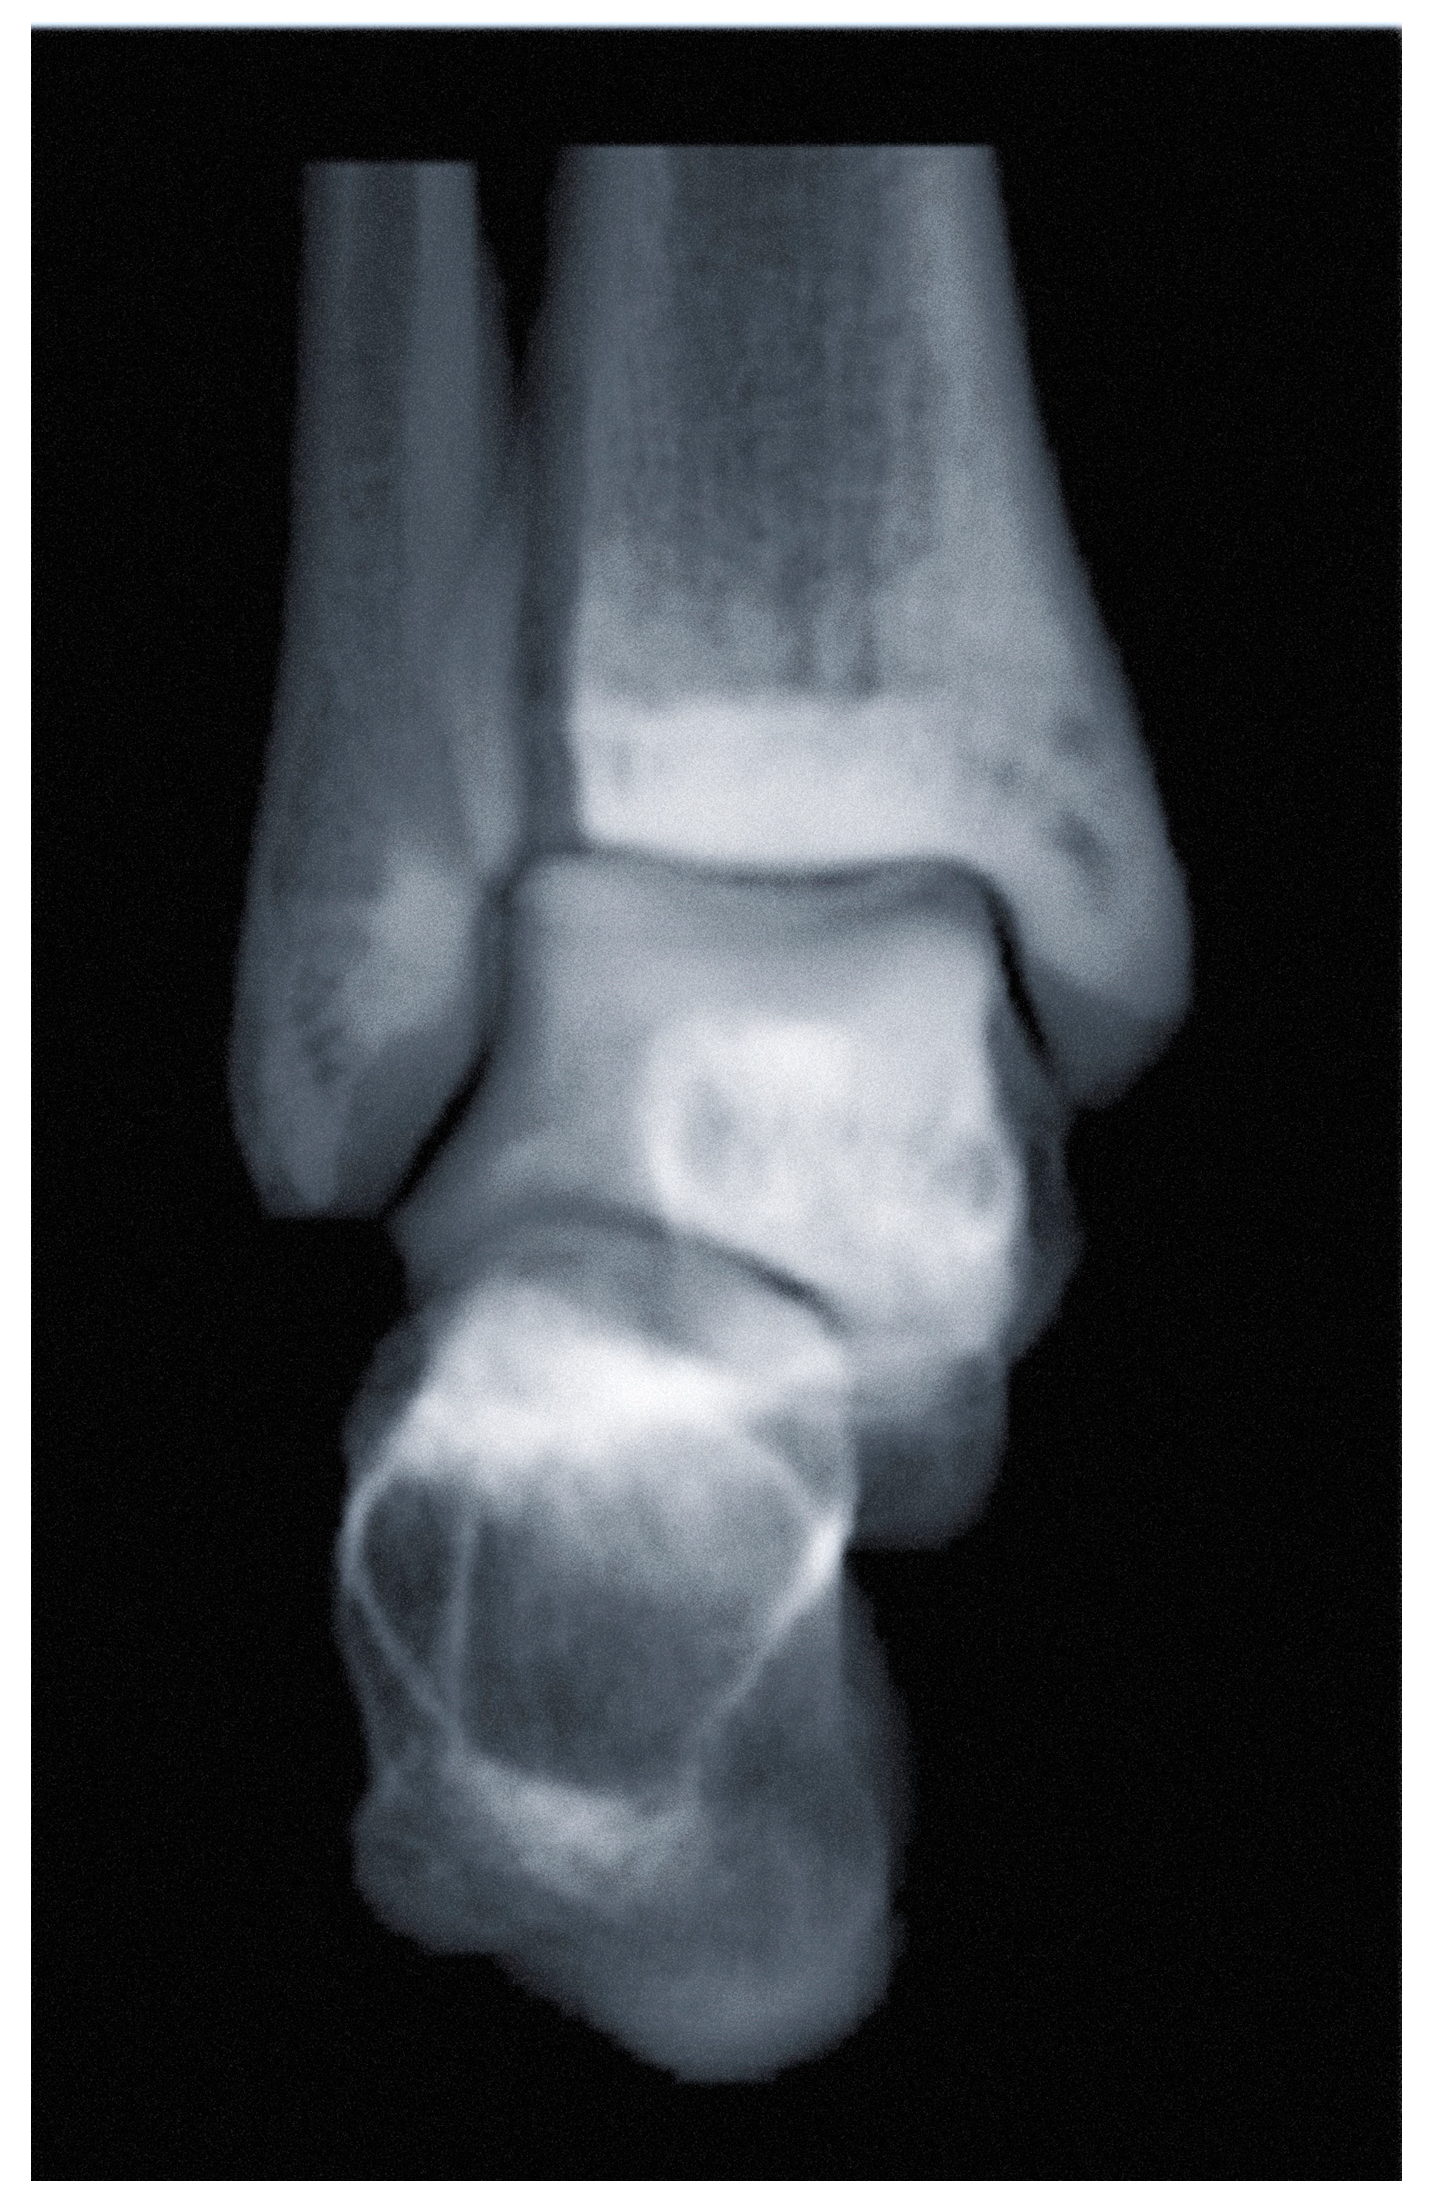

3.1. Ankle Osteoarthritis

3.1.1. Diagnosis